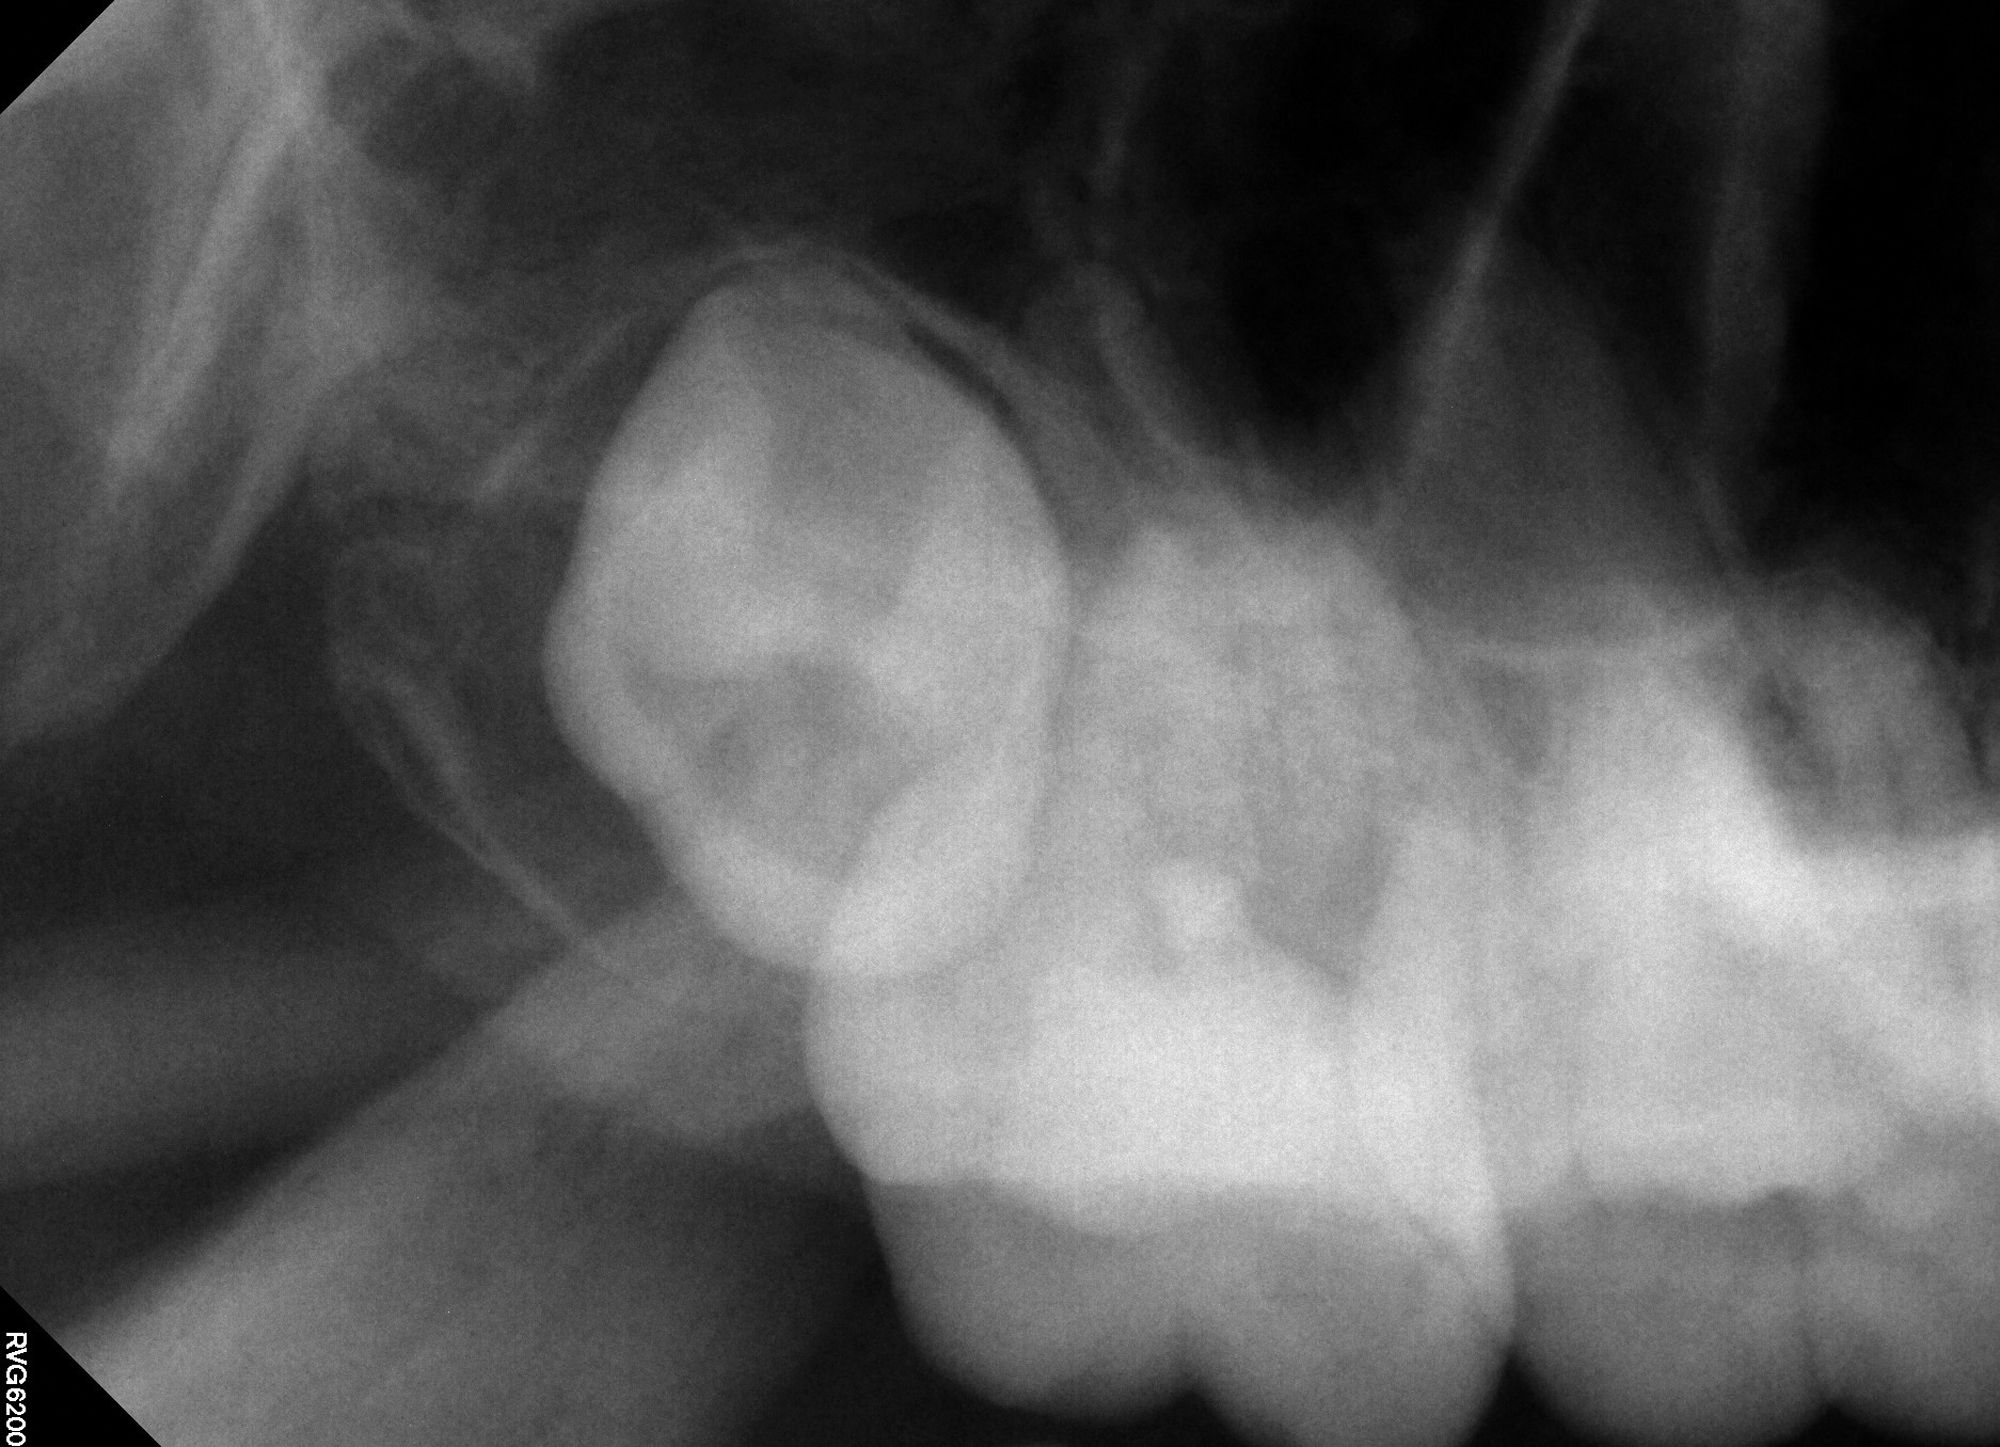

Figure 2A

Figure 2B. Deep caries associated with signs and symptoms of reversible pulpitis in tooth No. 29 (A) resulted in hyperemic pulp tissue extending throughout the pulp chamber, warranting bioceramic pulpotomy to achieve hemostasis (B).